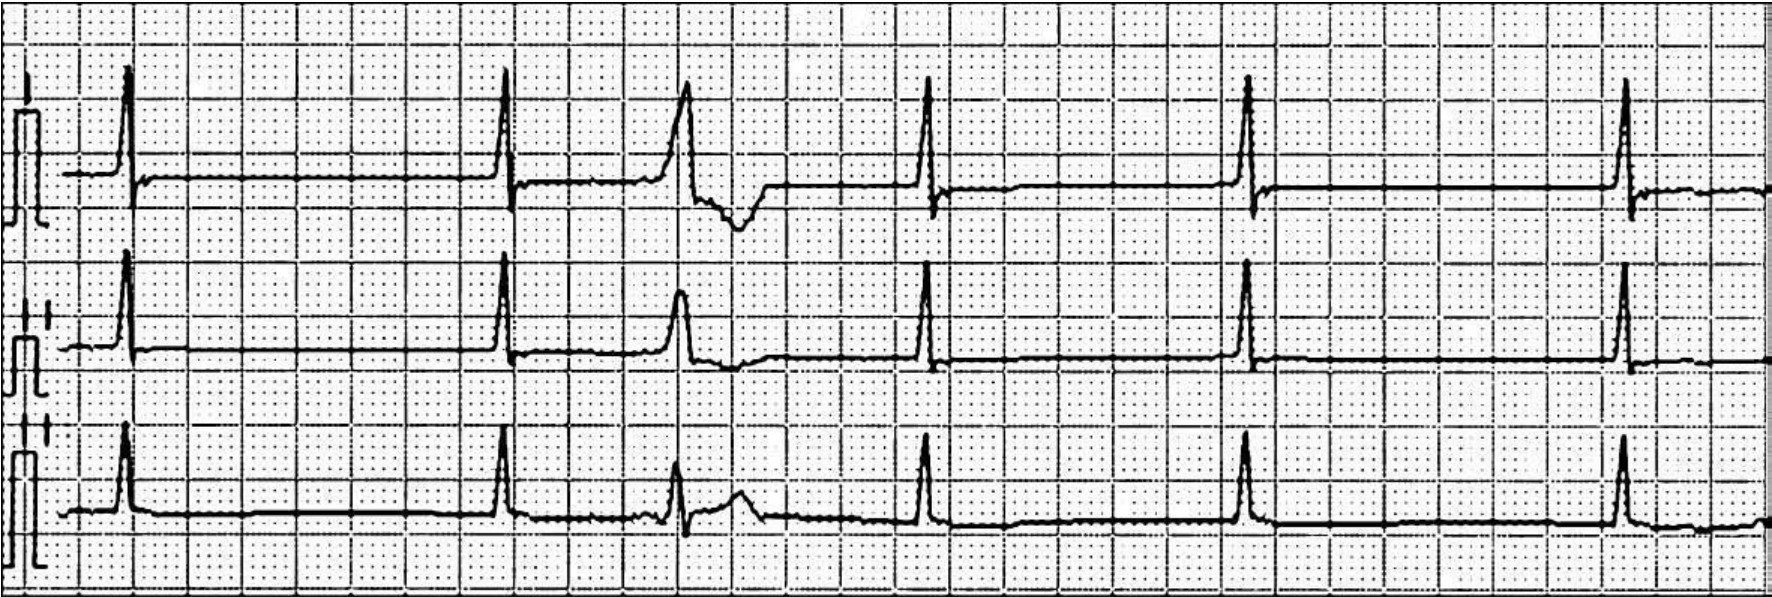

Hoffman等认为,隐匿性传导与心脏特殊传导组织内的递减性传导和不应期不均一有关。当激动落在传导组织的绝对不应期转变到相对不应期的过渡阶段,即“临界相”时,心脏传导组织应激能力极弱,产生的除极电位较低,这种低弱电位向邻近组织传导时,其动作电位进行减弱,传导速度也进行减慢,终于完全停止传导,导致激动不能传导至心房或心室,体表心电图中无P波和QRS波群。但由于它激动了一部分交界区组织,产生了一次新的不应期,影响下一次接踵而致的激动传导,产生传导延缓、传导阻滞、加速或折返等心律失常。另外,心脏传导组织不应期的不均一性也可引起隐匿性传导(图43-1)。

img747

图43-1 隐匿性传导示意图